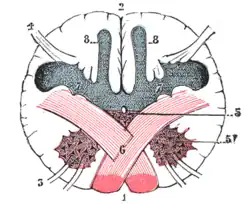

Section of the medulla oblongata at the level of the decussation of the pyramids.

Section of the medulla oblongata at the level of the decussation of the pyramids.